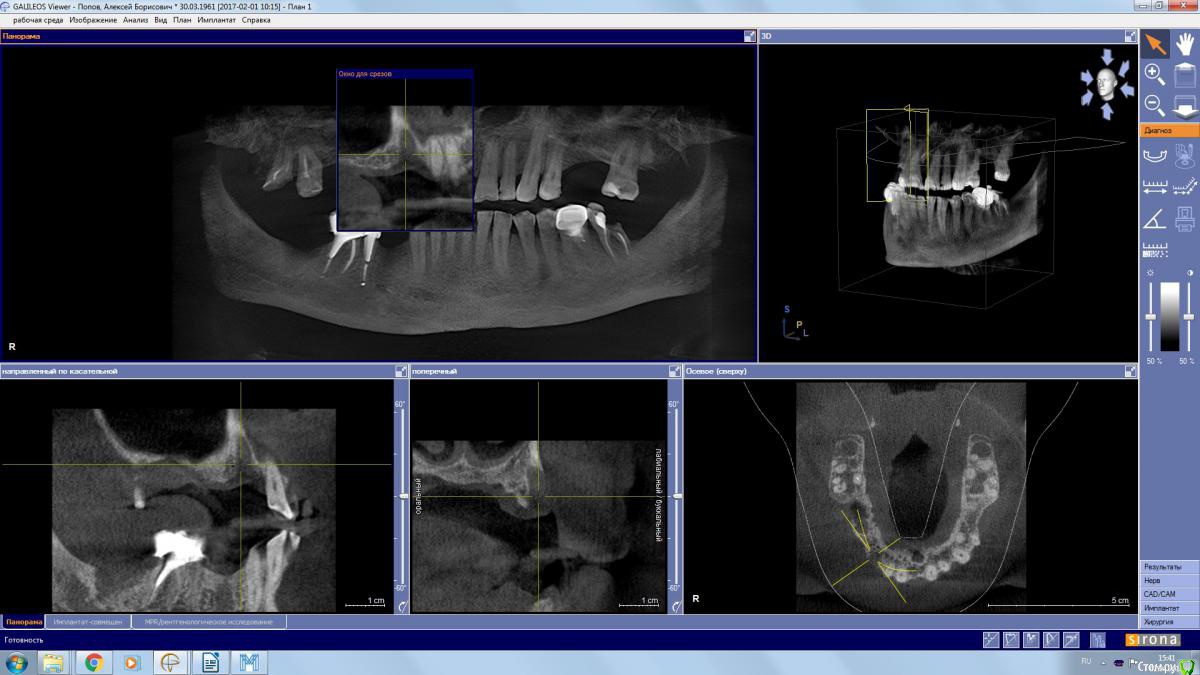

kamranchick Опубликовано 2 апреля, 2017 Поделиться Опубликовано 2 апреля, 2017 (изменено) Пациент обратился с целью восстановления жевания.удалял 16 зуб в поликлиннике, ему долбили, потом в ЧЛХ доставали что то).На кт вот такая ситуация, как посоветуете поступить? PS 1.7 и 1.8 зуб удалил. Изменено 2 апреля, 2017 пользователем kamranchick Ссылка на комментарий

stommm Опубликовано 2 апреля, 2017 Поделиться Опубликовано 2 апреля, 2017 Где окно расщеплять лоскут остро что бы часть осталась на поверхностном лоскуте, часть ввернуть в синус. Наверное можно совместить с НКР фронтальнее. З.Ы. сложно по сироне что-то планировать, самый неудобный вьюер имхо 1 Ссылка на комментарий

колесников Опубликовано 2 апреля, 2017 Поделиться Опубликовано 2 апреля, 2017 А в чем вопрос? Пазуха чистая,можно пробовать . Ссылка на комментарий

kamranchick Опубликовано 2 апреля, 2017 Автор Поделиться Опубликовано 2 апреля, 2017 Да дыры какие то и на окклюзионной поверхности и сбоку) это и отпугнуло Ссылка на комментарий

егорджан Опубликовано 26 декабря, 2017 Поделиться Опубликовано 26 декабря, 2017 слева главное штырь торчит на сантим в пазуху и ничего Ссылка на комментарий

kamranchick Опубликовано 26 декабря, 2017 Автор Поделиться Опубликовано 26 декабря, 2017 слева главное штырь торчит на сантим в пазуху и ничегоштырь торчит 10 лет, полет нормальный, закапсулировался, у нас в стране имплантаты вгоняют так в пазуху и так же все хорошо() Ссылка на комментарий